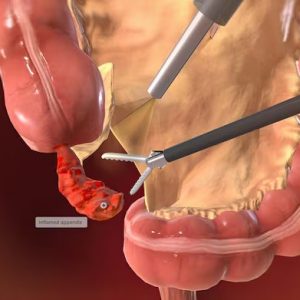

Laproscopic Appendectomy

Laparoscopic appendectomy is a safe and advanced keyhole surgery to remove an inflamed appendix with minimal discomfort, faster recovery, and reduced scarring.